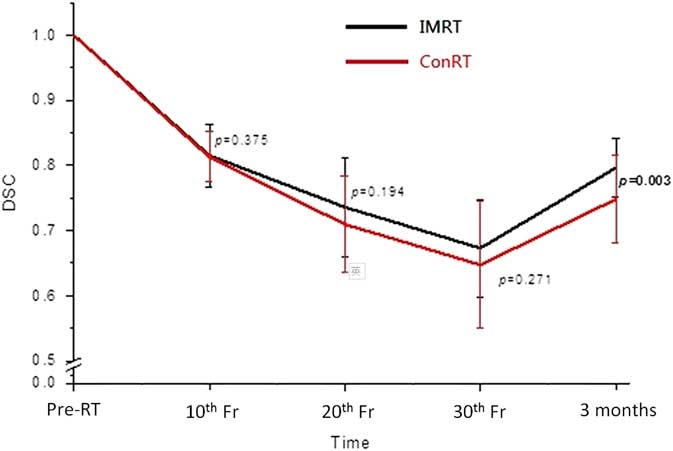

Percentage parotid volume change

The mean parotid volume in both groups decreased with a maximum reduction of 35% at the 30th fraction (Figure 3). There were no significant differences between the ConRT and IMRT groups from 10th to 30th fractions. Volume recovery was observed in both groups at 3 months following RT with significantly greater recovery in the IMRT group (p=0·007). The trend of DSC was similar to that of the volume change. It decreased from pre-treatment to 30th fraction and partially recovered at 3 months after treatment (Figure 4). Significant difference between ConRT and IMRT was only noted at the 3 months post-RT interval with the IMRT group demonstrating a better restoration of the original shape (p=0·003).

Figure 4 Comparison of the mean dice similarity coefficients (DSC) of parotid glands between conventional radiotherapy (ConRT) and intensity-modulated radiotherapy (IMRT) plans over the radiotherapy course up to 3 months after treatment. Note: The horizontal lines indicate the error bars.

With regard to the geometric changes of the parotid gland during radiotherapy, our study demonstrated that there were no significant differences between patients treated by ConRT and IMRT. For both groups of patients, the parotid gland demonstrated continuous shrinkage and medial migration during the treatment course. They were reflected by the increase of Δ%V, DSC and TVD from pre-treatment to 30th fraction, respectively. The shrinkage of parotid glands during radiotherapy has been reported in previous studiesReference Barker, Garden and Ang 16 , Reference Zhang, Lin and Wu 17 and it was mainly caused by the loss of gland parenchyma and acinar cell atrophy due to high dose radiation.Reference Radfar and Sirois 18 , Reference Wang, Yan and Zhang 19 The volume reduction of the parotid gland subsequently changed its shape and therefore resulted in a similar trend in DSC as for Δ%V. This medial migration of the parotid gland during radiotherapy was caused by the shrinkage of radiosensitive NP tumour, which was situated medially to the parotid gland and created space for the parotid gland to move in. Another associated factor could be due to the weight loss of the patients, whose head size became smaller leading to the lateral structures moved closer to the mid-plane. Actually such medial movement of the parotid gland during radiotherapy course has been reported by some studies.Reference Fung, Wu and Teo 20 , Reference Barker, Garden and Ang 21 Our study has shown that NPC patients generally had gradual weight loss during a course of radiotherapy. This was reflected by the reduction of the lateral head dimension. The phenomenon of weight lost, however, may vary across other institutions depending on nutritional support given. This is a common phenomenon for head and neck cancer patients as a result of poorer nutritional status due to radiation induced oral mucositis and xerostomia. The effect would be compounded with concurrent chemotherapy, which is commonly applied for stage II disease or above for NPC patients.

Due to the better target dose conformity in IMRT plans, they were more effective in sparing the parotid gland than the conRT plans in NPC patients. This was proven in our study in which the average mean parotid dose of the IMRT group was about 12 Gy lower than that of the ConRT group. This was also the reason that higher prescribed dose to the target could be given in IMRT than in ConRT plans, which subsequently led to better tumour control.Reference Au, Ngan and Ng 22 , Reference Yan, Cao and Wang 23 Although the geometric changes of the ConRT group appeared relatively greater than that of the IMRT group during the radiotherapy course, their differences did not reach significance. This implied that the extra dose delivered by the ConRT to the parotid gland did not lead to significant geometric change during the treatment course. The possible reasons were because the mean doses of both groups had already exceeded the recommended tolerance mean dose of 25 Gy,Reference Deasy, Moiseenko and Marks 24 the extra dose delivered by the ConRT would not cause significant increase of parotid gland damage. Nevertheless, the results obtained at 3 months after treatment demonstrated that IMRT plans showed better recovery of parotid gland volume, shape and centroid position. For instance, the mean parotid volume returned to 85% of pre-treatment volume in IMRT group, compared with 75% in ConRT group. This indicated that although the rate of parotid gland damage was similar during the course of radiotherapy, the rate of recovery after completion of treatment was different between the two techniques. It has been reported that parotid recovery took place after completion of radiotherapyReference Hey, Setz and Gerlach 25 which were in line with the geometric changes obtained in our study. In addition, study by Hey et al.Reference Hey, Setz and Gerlach 25 reported that the recovery process of the parotid gland could be dose dependent. It was also proposed in some studies that stem cells in the parotid gland were responsible for the post-RT repair if they were not eliminated in the treatment course.Reference Feng, van der Zwaag, Stokman, van Os and Coppes 26 As the more conformal IMRT plans are better equipped to limit the high dose to a smaller volume, and deliver lower mean dose to the gland, it can help to preserve more stem cells in the gland and facilitate better recovery. The improved recovery of the parotid gland in the IMRT cohort may be attributed to this improved opportunity for stem cell recovery.